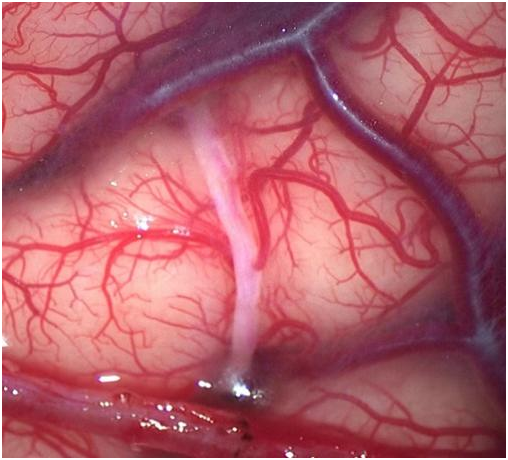

这场手术的主刀医生是郑州大学附属郑州中心医院高新院区神经外科青年医师吕国伟 。 穿刺、提拉、吻合 , 动作行云流水、一气呵成 。 10针结束 , 松开血管阻断夹 , 血流通过!原本苍白的血管立刻变红 , 所有人提着的心终于放下 。

医生在用一根比头发丝儿还细的线在莉莉颅内0.8毫米的血管上“穿针引线”

0.8毫米血管上缝合10针 , 第二次手术完成顺利!

神经外科青年医师吕国伟正是莉莉的主刀医生 , 别看他和莉莉年纪一样 , 可是“老资历”了 , 已经成功完成70余例该项“揭榜挂帅”手术 。 他是该院首批获得四级手术资质授权的青年医师之一 , 尤其擅长脑血管疾病 , 如烟雾病、颅内动脉瘤、脑动静脉畸形等外科治疗 。

手术日 , 吕国伟实力强悍 , 跟夫妻俩又是同龄人 , 莉莉和柴哥非常信任他 。 很快莉莉接受了左侧“颅内外血管联合搭桥术” , 手术顺利 , 术后恢复很好 。